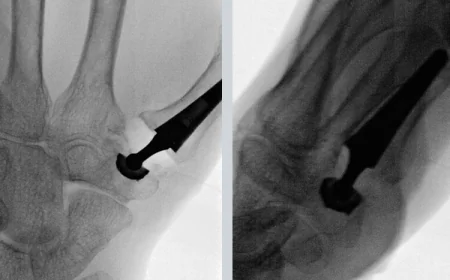

CMC Joint Replacement Surgery – Restore Thumb Mobility with Expert Care in London

CMC Joint Replacement Surgery – Restore Thumb Mobility ...

Are you struggling with thumb pain, stiffness, or arthritis? Regain your hand st...